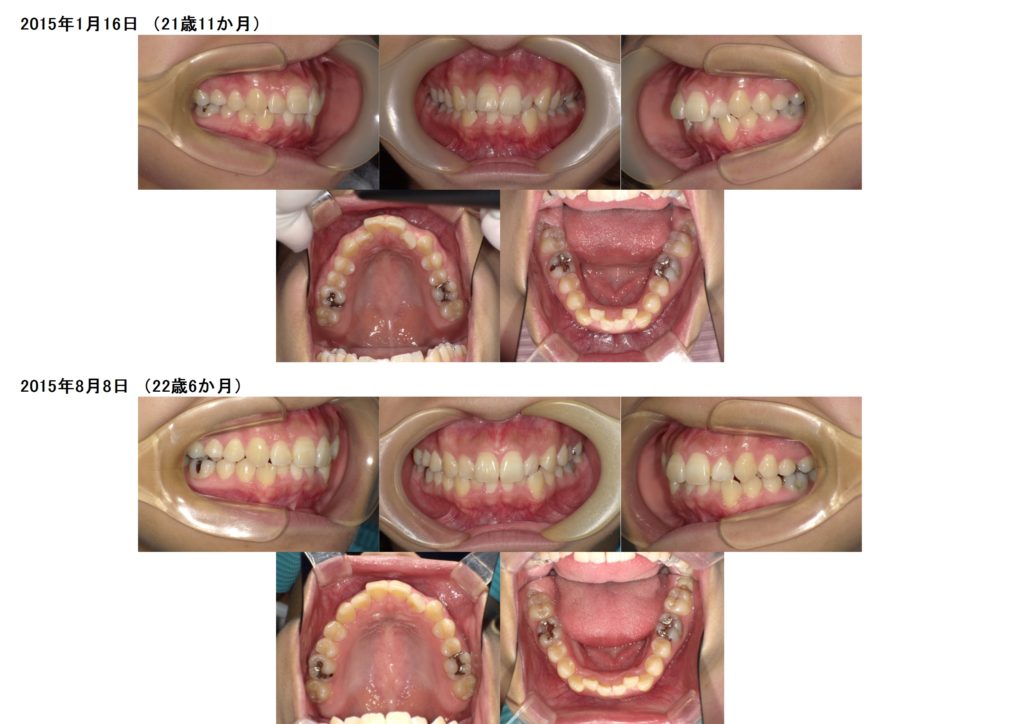

医院ブログ 2020/10/09先天性欠如の方のインビザライン治療例